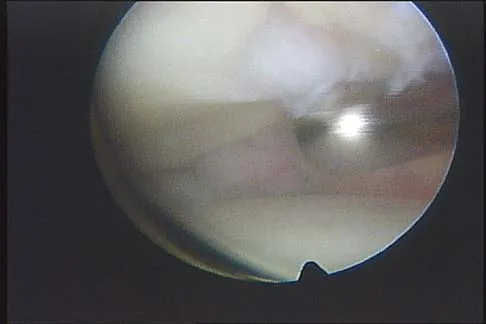

What is the most common arthroscopic finding of internal impingement in an overhead athlete?

Explanation